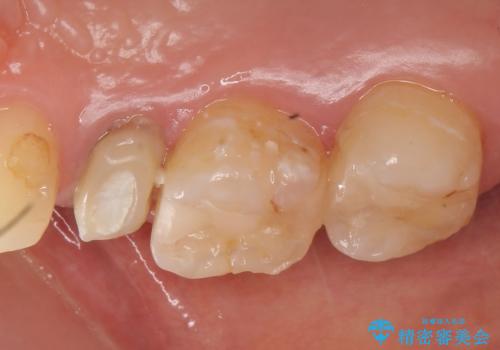

右上5は再根管治療を行い症状の緩解を確認後、オールセラミッククラウンによる補綴を行いました。

右上6、7番目の歯もしみるとのことだったので古い樹脂及び虫歯を除去後、オールセラミッククラウンによる補綴を行いました。

今回用いたオールセラミッククラウンはジルコニアフレームという白い素材の上にセラミックを盛っているため、審美性が非常に高いのが特徴です。

また、ジルコニアは人工ダイヤモンドの材料にも使われているほど高い強度を持っており、そのためオールセラミッククラウンは審美性だけでなく、奥歯やブリッジの補綴も可能とするクラウンです。